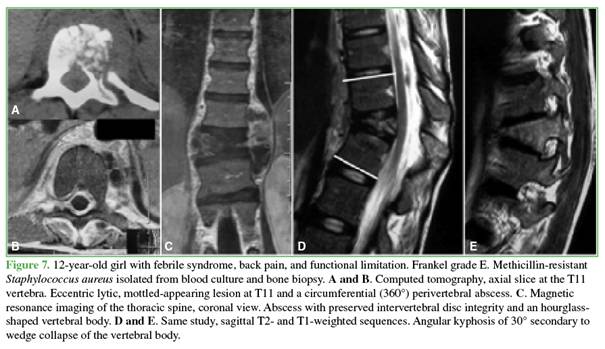

On

computed tomography, bone lesions exhibited a lytic or mottled appearance, with

asymmetric distribution and poorly defined margins. One patient developed

angular kyphosis due to wedging of T11, which required delayed pedicle subtraction osteotomy (Figure 7).

Magnetic

resonance imaging showed hypointense signal on T1-weighted sequences and

hyperintense signal on T2-weighted and STIR sequences, with gadolinium

enhancement. In patients with bone involvement and negative blood cultures,